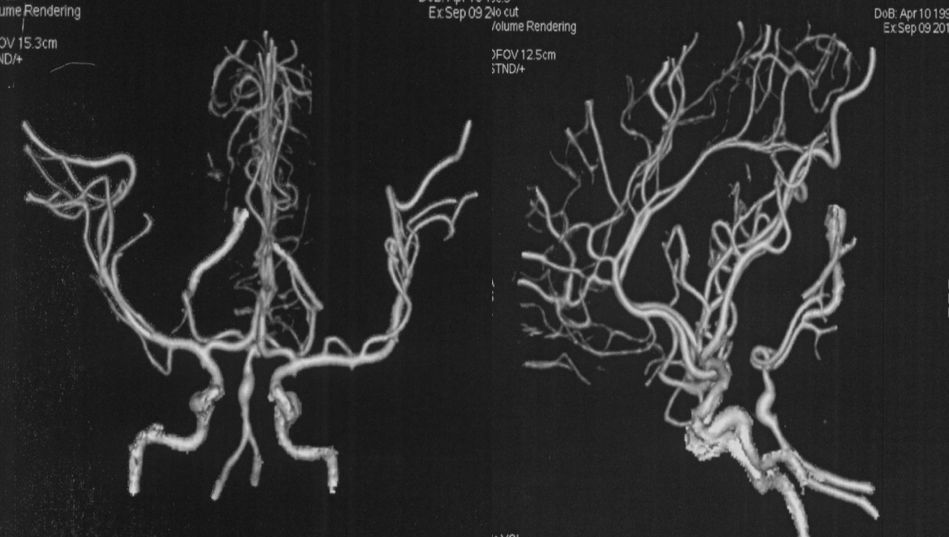

当地医院 CTA:基底动脉中上段瘤样扩张(图2)。

图2

当地医院DSA:基底动脉中上段夹层动脉瘤(2019-09-10)(图3)。

图3

当地医院MRA:基底动脉中上段夹层动脉瘤(2019-09-16)(图5)。

图5

本院DSA:基底动脉巨大夹层动脉瘤,双侧后交通动脉未见明显开放(图6)。

图6

本院 DSA三维血管重建(2019-10-10)显示:基底动脉巨大夹层动脉瘤(图7)。

图7